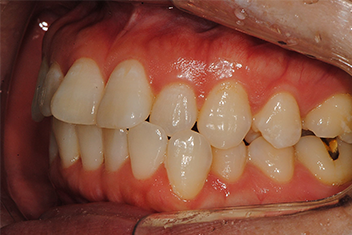

앞니 돌출 해소 케이스1

치료 기간16개월

심한 앞니 돌출을 투명교정으로 점진적으로 개선